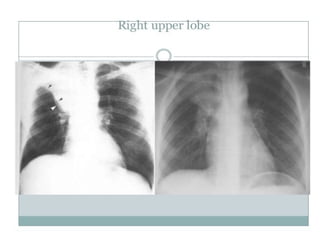

• RUL consolidationConfined

by horizontal fissure inferiorly and upper

half of oblique fissure posteriorly ,may

obscue right upper mediastinum

rul consolidation